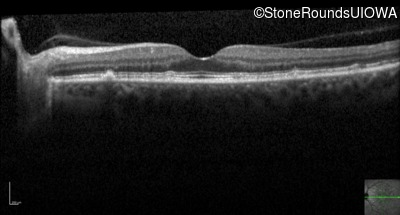

Optical Coherence Tomography - Left - 20/20 -1

Exemplar / OCT Stack

OCT Stack